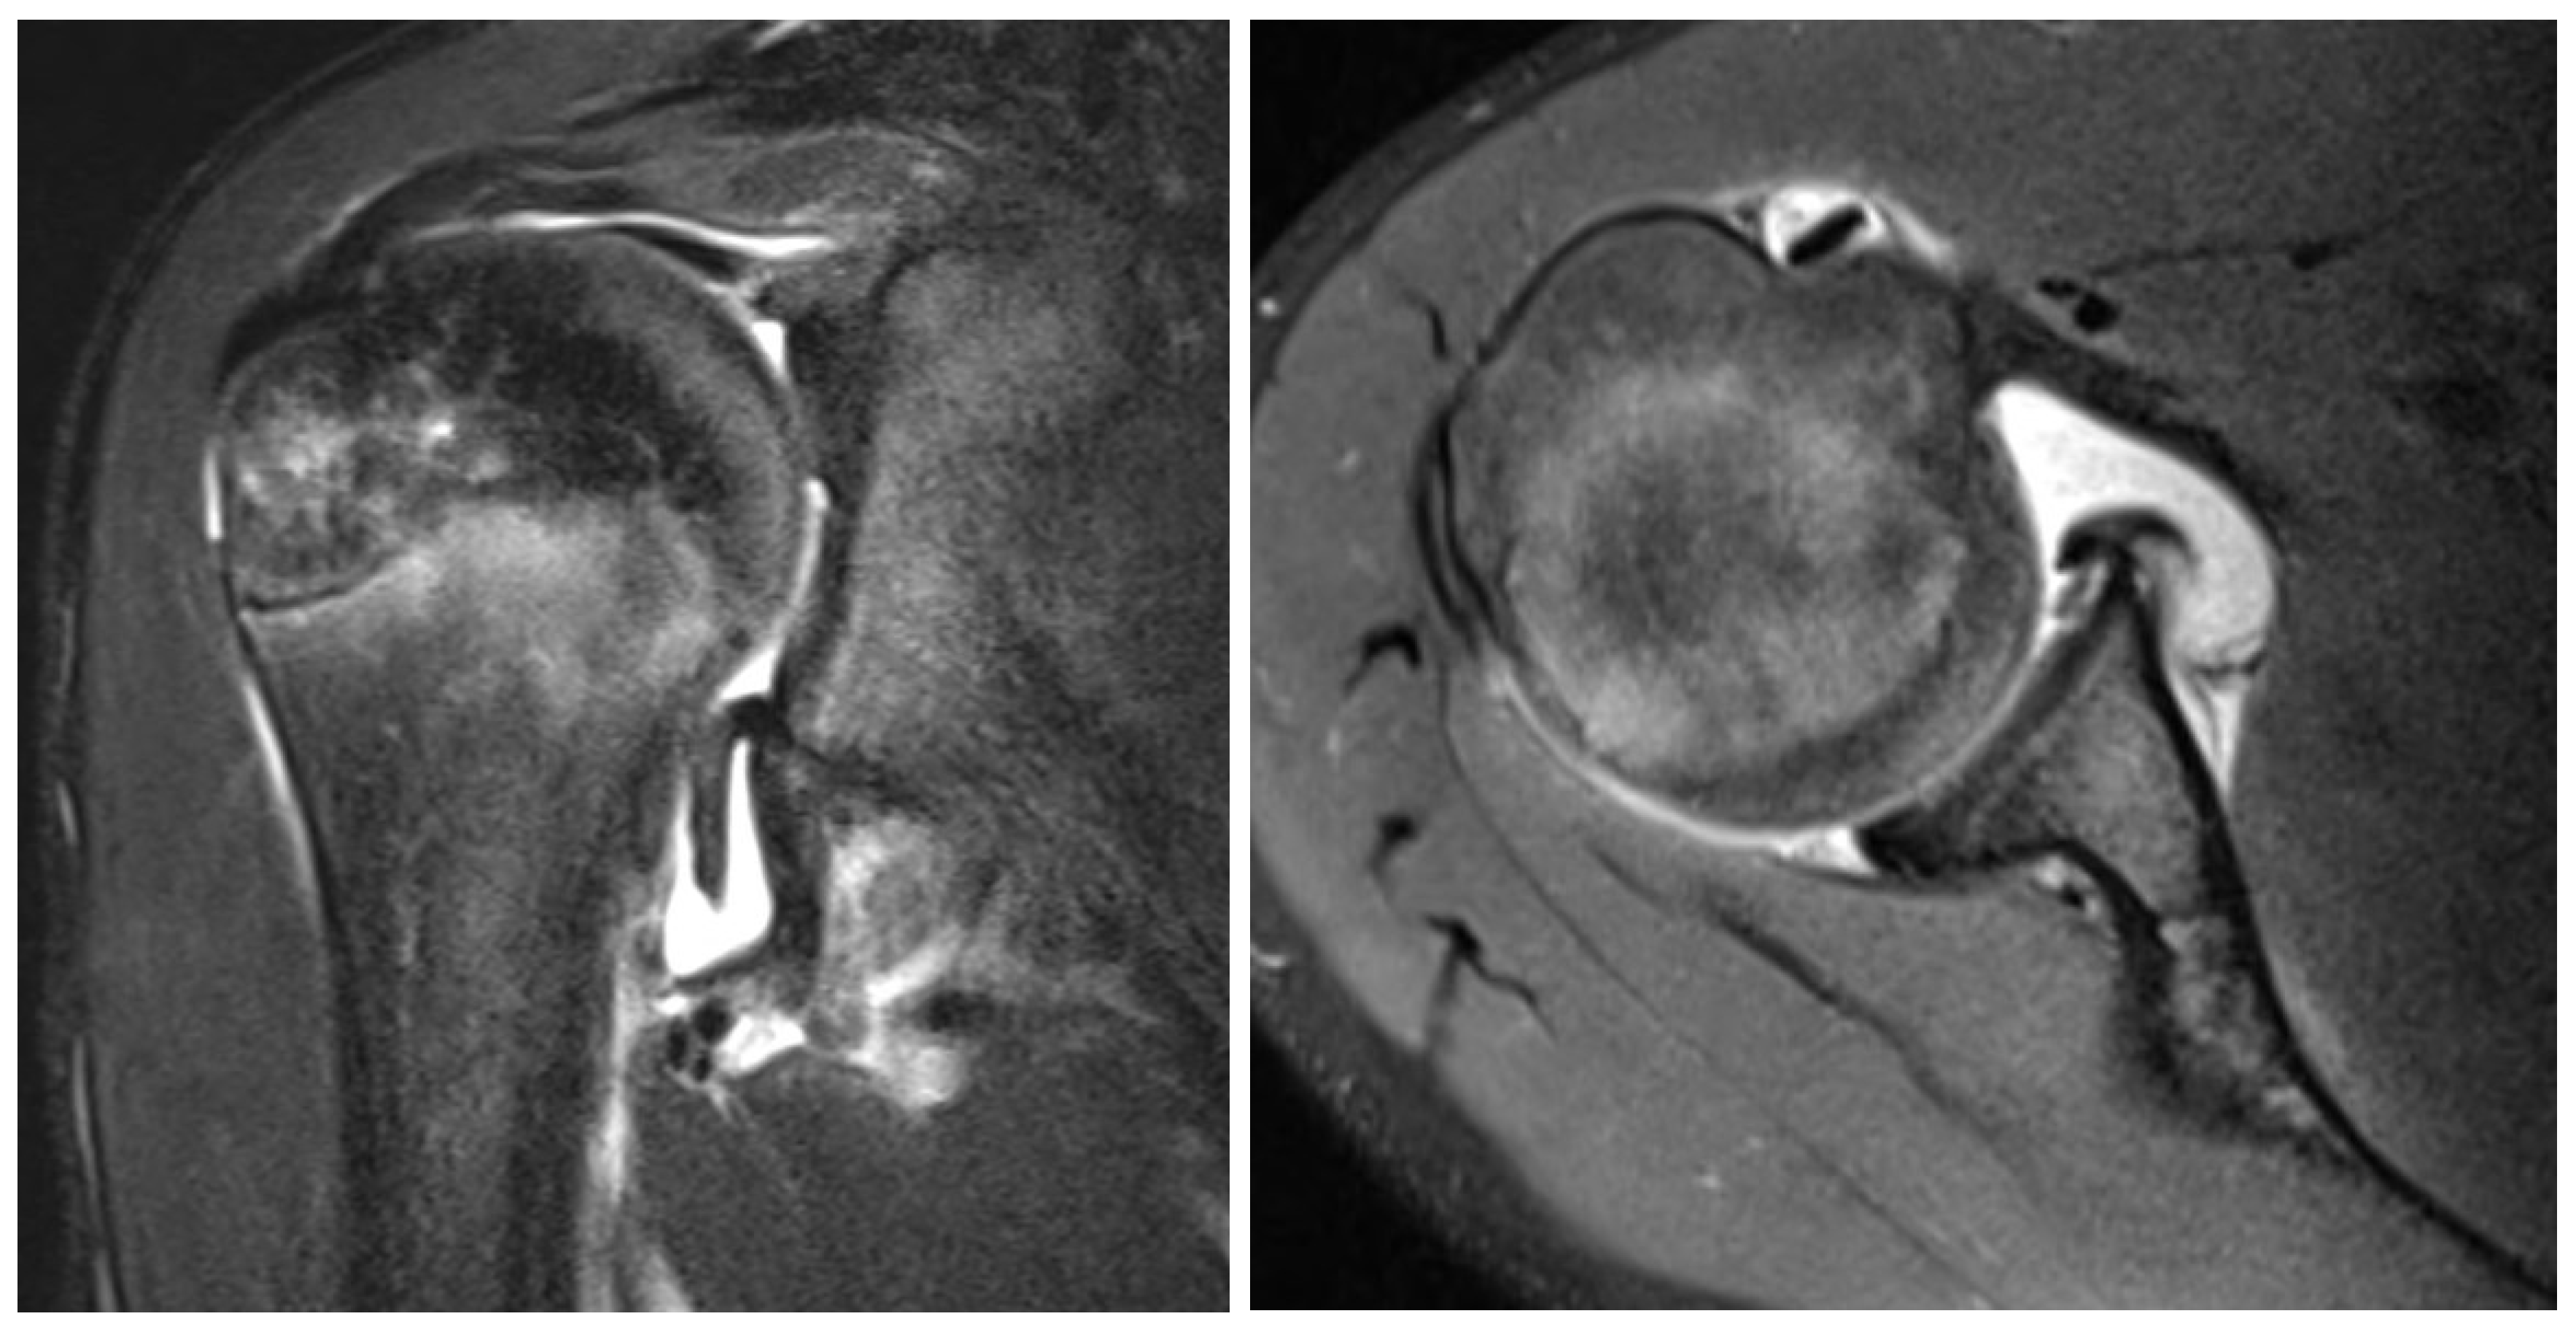

Figure 2. T2 weighted MRI coronal (left) and axial (right) slice of a 13 year old boy with GLAD, SLAP, HAGL and labral lesions.